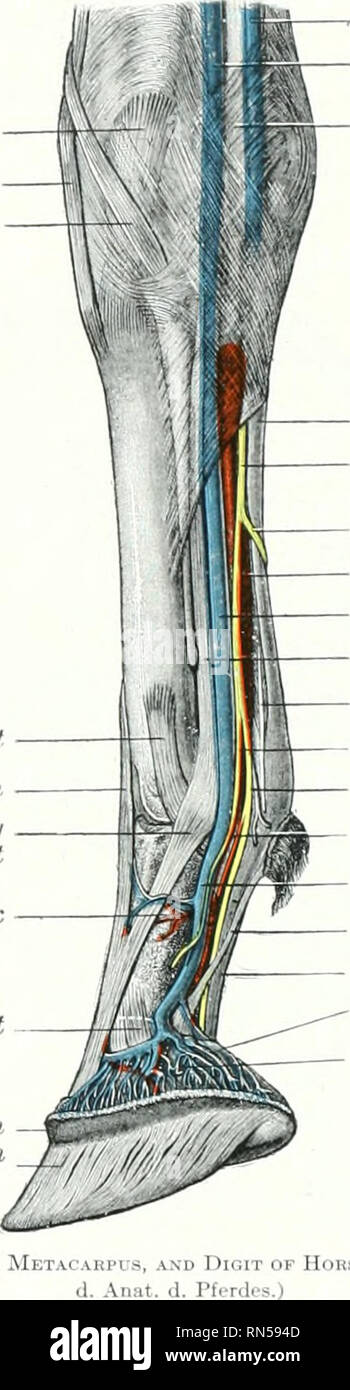

ar.inspiredpencil.comVM602 - Gross Anatomy (Annular Ligament Of Horse) Diagram | Quizlet

ar.inspiredpencil.comVM602 - Gross Anatomy (Annular Ligament Of Horse) Diagram | Quizlet

Annular Ligaments In The Horse Forelimb Diagram | Quizlet

quizlet.comPart 4: Distal Thoracic Limb – Dissection Lab Guide For Ungulate Anatomy

quizlet.comPart 4: Distal Thoracic Limb – Dissection Lab Guide For Ungulate Anatomy